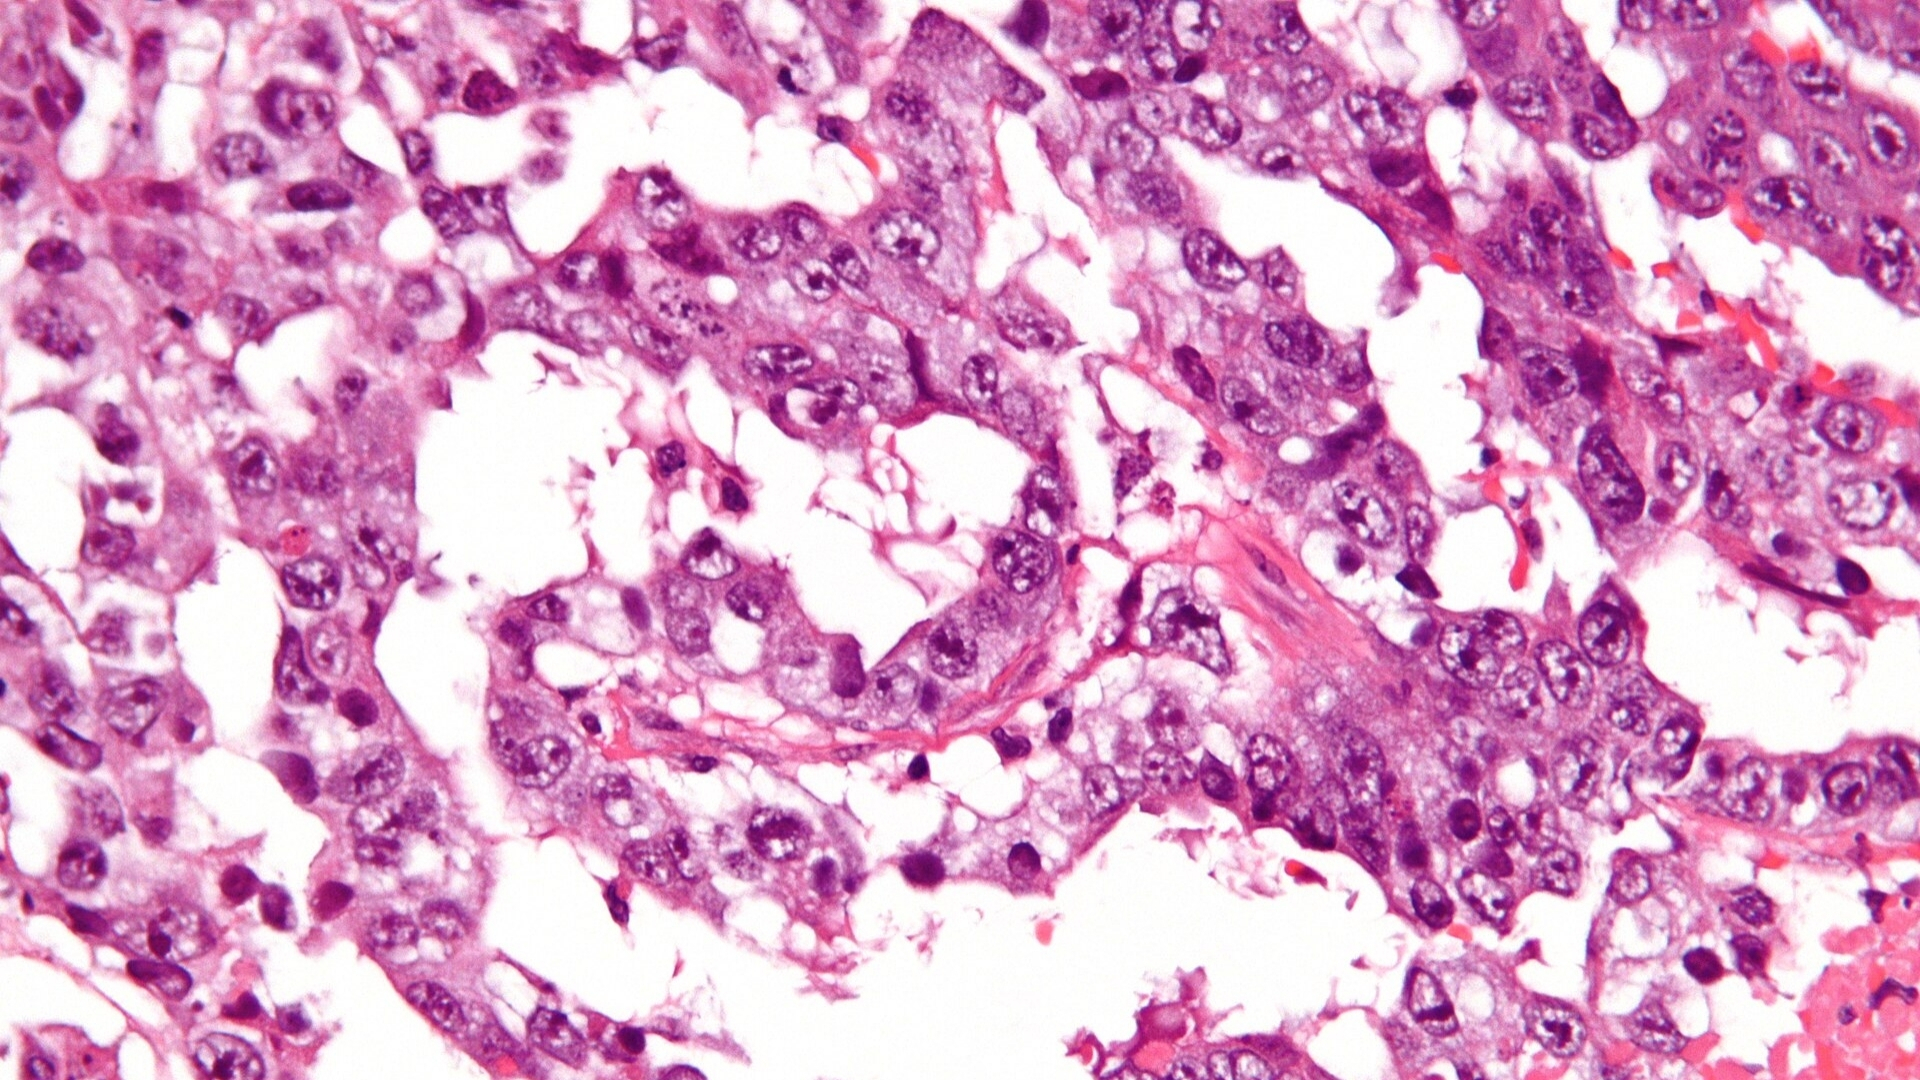

生殖細胞腫瘤 (Extragonadal Germ Cell Tumor,EGCT) 是起源於生殖細胞的一種獨特亞型癌症,生殖細胞通常是負責生殖的細胞。與卵巢或睪丸所產生的傳統生殖細胞腫瘤不同,這些癌症發生在主要生殖器官之外,通常表現在胸部、腹部、腦部或縱膈等部位。

EGCT 生物特性的核心是對失調代謝通路的基本依賴。與許多侵襲性癌症類型一樣,EGCT 細胞也呈現沃伯格效應 (Warburg effect)--一種獲頒 2019 年諾貝爾生理學或醫學獎的現象 (Gregg Semenza 教授)--癌細胞即使在有氧的情況下,也會優先以增加的速度消耗葡萄糖,最高可達正常消耗速度的 200 倍。